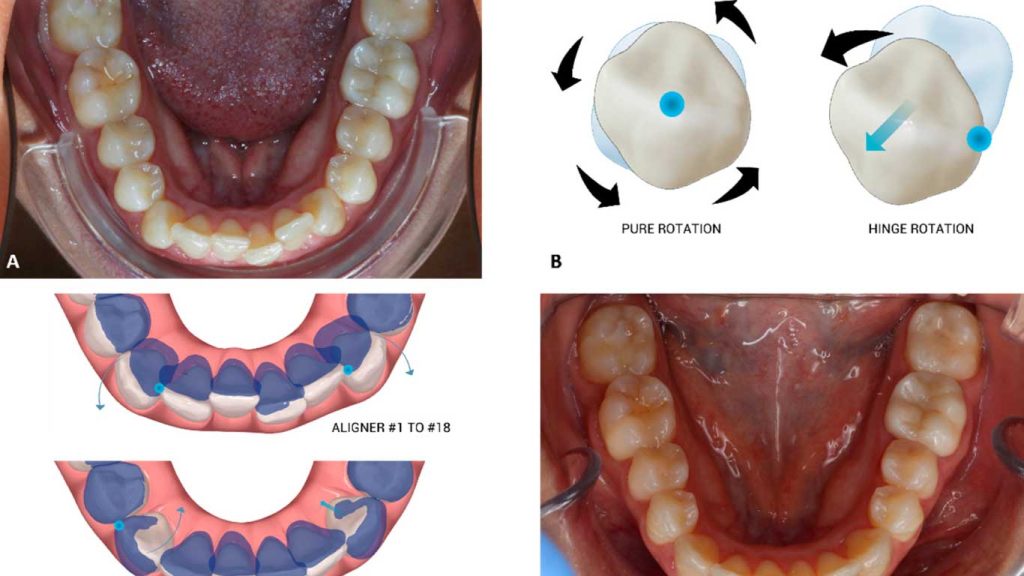

چرخش دندان به وضعیتی اطلاق می شود که در آن یک یا چند دندان حول محور طولی خود چرخیدند و از راستای طبیعی خود در قوس دندانی خارج شدند. جابجایی دندان نیز به معنای قرارگیری دندان در موقعیتی نادرست نسبت به دندان های مجاور یا قوس فکی است. درمان چرخش و جابجایی دندان با هدف بازگرداندن این دندان ها به موقعیت صحیح انجام می شود.

دندان چرخیده، دندانی است که به جای قرار گرفتن در یک راستای مستقیم و هماهنگ با سایر دندان ها، به دور خود چرخیده است. این چرخش می تواند خفیف (کمتر از ۴۵ درجه) یا شدید (بیش از ۴۵ درجه) باشد. درمان چرخش و جابجایی دندان برای این موارد ضروری است.

دندان جابجا شده، دندانی است که از موقعیت ایده آل خود در قوس دندانی منحرف شده است. این جابجایی می تواند به سمت گونه، زبان، بالاتر یا پایین تر از خط لثه یا حتی به فضای خالی ناشی از نبود دندان دیگر باشد. تشخیص صحیح برای درمان چرخش و جابجایی دندان اهمیت دارد.

هرچند هر دو وضعیت نشان دهنده نا مرتبی دندان ها هستند، اما چرخش به پیچش دندان حول محور خود اشاره دارد، در حالی که کج بودن ممکن است صرفاً انحراف زاویه ای بدون چرخش کامل باشد. با این حال، هر دو مشکل می توانند بخشی از یک طرح درمان دندان چرخیده یا جابجا شده باشند.

ارتودنسی ثابت با بریس های فلزی یا سرامیکی

ارتودنسی نامرئی با الاینر های شفاف

ارتودنسی نامرئی یا الاینر ارتودنسی، گزینه ای محبوب برای افرادی است که به دنبال درمانی کمتر قابل مشاهده برای درمان چرخش و جابجایی دندان هستند. این پلاک های شفاف و متحرک به تدریج دندان ها را حرکت می دهند.